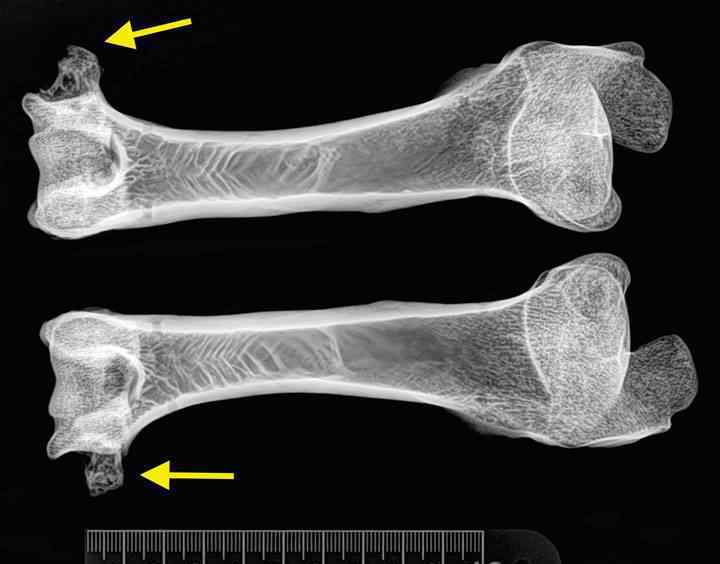

图 | 科学研究工作人员对克隆羊多利的骨骼开展了 X 光拍片子,以分辨她是不是由于复制而身患风湿病

图 | 从 X 光剧中大家能看得出,多利的肱骨一端拥有 一些由风湿病造成的损害(淡黄色箭头符号),可是此外一端则十分光洁完美无瑕。而这种损害与此外一只与多利同年龄的当然小羊十分相似,表明复制并沒有恶变多利的风湿病。